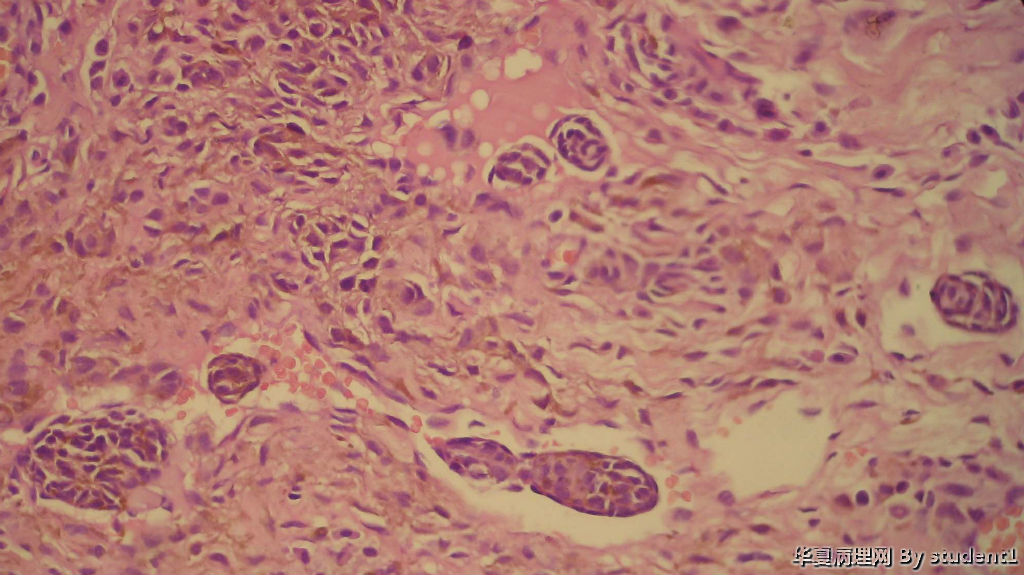

男,35岁,结膜痣切除

送检小组织,直径0.2cm

请教:是否侵犯血管淋巴管?有何意义?

结膜痣?图4

名称:图4

描述:40倍

皮内痣

考虑皮内痣,那些痣细胞巢周围未见内皮细胞,不考虑侵犯血管淋巴管。